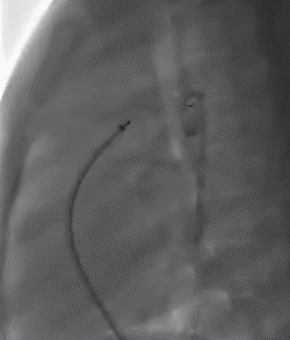

早期动脉导管未闭的常规治疗方式为开胸结扎手术,但随着介入治疗的发展逐步被淘汰,目前大部分动脉导管未闭均可采取动脉导管未闭介入封堵技术进行治疗。常规的封堵手术是使用蘑菇伞样的封堵器,锚定在主动脉和肺动脉之间的动脉导管中,阻断主动脉和肺动脉之间的异常血流。在X线下可以看到封堵器锚定在动脉导管内,一般锚定较为稳固不会发生移位的(图2)。

图2. 动脉导管未闭介入封堵术示意图